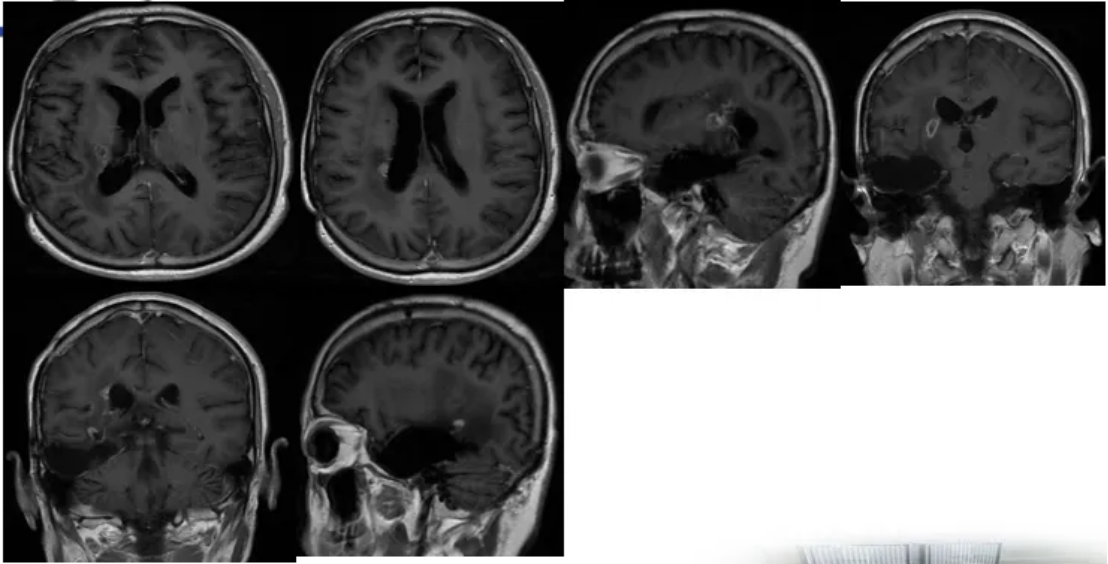

2022-9-19脑部MRI随访复查:右侧颞叶胶质瘤术后,右侧额叶侧脑室前角旁结节,右侧基底节区后部片状异常信号,较前(2022-7-1)强化程度减低;右侧脑室周围及胼胝体压部缺血灶,较前片相仿;右侧额颞部少许硬膜下积液,较前稍吸收;右侧基底节区陈旧性腔梗灶(图5)。

2022-11-30脑部MRI随访复查:右侧颞叶胶质瘤术后,右侧额叶侧脑室前角旁结节此次未见,右侧基底节区后部片状异常信号,较前(2022-09-19)强化程度减低;右侧脑室周围及胼胝体压部缺血灶,较前片相仿;右侧额颞部少许硬膜下积液,较前相仿;右侧基底节区陈旧性腔梗灶(图5)。

2023-1-28脑部MRI随访复查:右侧颞叶胶质瘤术后,右侧基底节区后部片状异常信号,较前(2022-11-30)范围基本相仿,建议定期复查;右侧脑室周围及胼胝体压部缺血灶;右侧额颞部少许硬膜下积液,较前相仿;右侧基底节区陈旧性腔梗灶(图5)。

2023-3-28脑部MRI随访复查:右侧颞叶胶质瘤术后;右侧基底节区后部片状异常信号,较前(2023-1-28)范围基本相仿,建议定期复查;右侧侧脑室周围及胼胝体压部缺血灶;右侧基底节区陈旧性腔梗灶(图5)。

图5靶向+替尼泊苷治疗前后脑部MRI图像